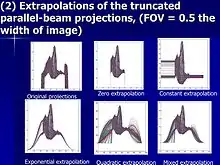

Extrapolation method

The response in the outside region can be a guess ; for example, assume it is

A solution of is written as , and is known as the extrapolation method. The result depends on how good the extrapolation function is. A frequent choice is

at the boundary of the two regions.[1][2][3][4] The extrapolation method is often combined with a priori knowledge,[5][6] and an extrapolation method which reduces calculation time is shown below.

Fast extrapolation

- ↑ S Zhao, K Yang, X Yang, Reconstruction from truncated projections using mixed extrapolations of exponential and quadratic functions, Journal of X-ray Science and Technology, 2011, 19(2) pp 155–72